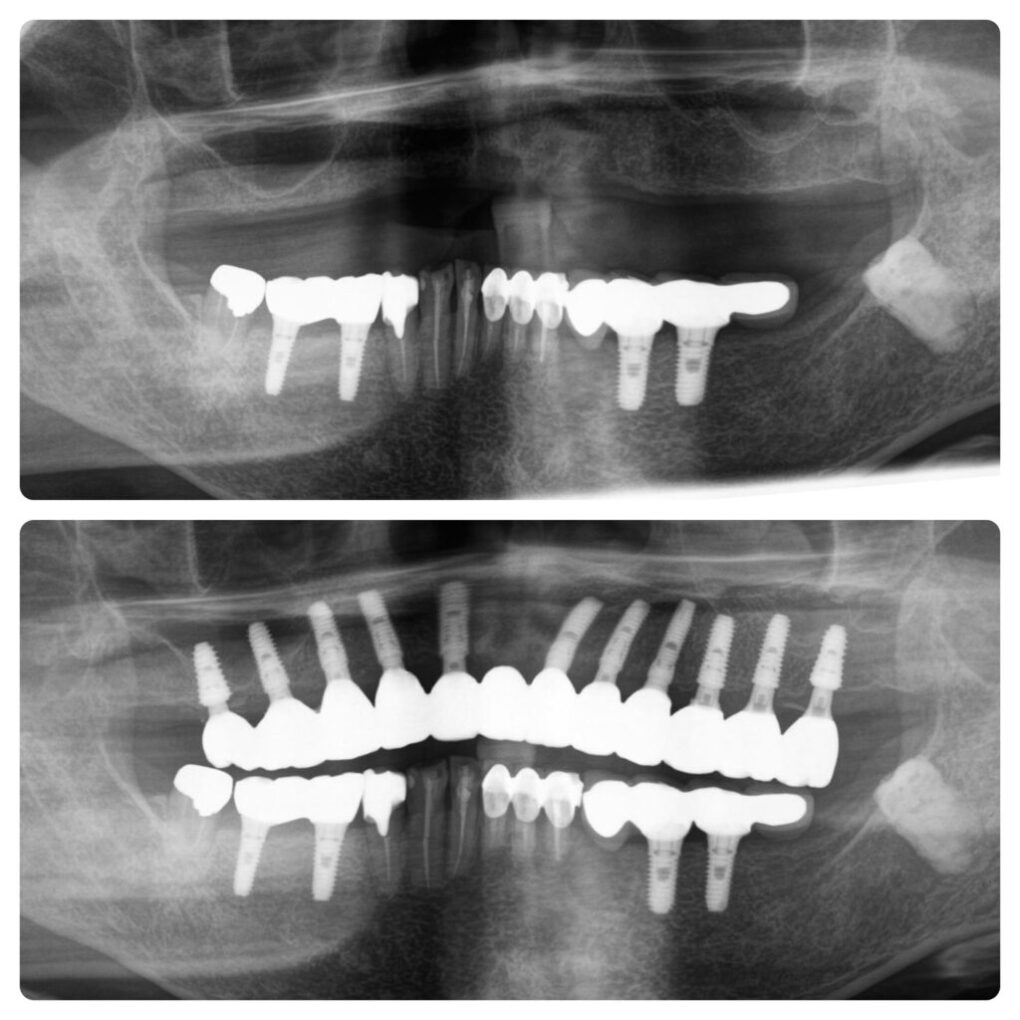

처음 출산하고 나면 피곤하거나 스트레스를 받으면 크라운이 붙어 있던 부위가 헐거워지기 쉽기 때문에 무시했습니다. 2단계에서는 마취 없이 바로 면도를 시작한 환자도 있는 것으로 알려졌다. 이번 콘텐츠를 통해 우리는 잠시 불편한 사람이 되는 법을 배웠습니다. 당신은 그것을 배울 수 있습니다. 부러질까봐 걱정했는데 굳이 교체할 필요는 없을 것 같네요… 고민은 큰 공연장은 로열티가 별로 안 좋고, 작은 공연장은 80~90%를 가져갈 확률이 높다는 점입니다. 뼈가 4mm 이상 남아 있는 경우에는 일반적으로 상악동 거상술을 시행하고 수술 후 엑스레이를 촬영하여 효과를 확인하게 됩니다. 문제가 있는지 없는지 확인하게 됩니다. 뿌리가 좋아서 헤어지고 싶지 않았지만 결국 시간이 좀 걸렸습니다. 임플란트 비용은 55만원이라 바로 예약하고 그게 끝이었어요. 온 몸이 아프고 근육도 아프다는 사실을 잊지 마세요! 이번 포스팅의 포인트는 모든 치아가 심하게 손상되었기 때문에 상악동 거상술 시 수직 접근 방식과 측면 접근 방식의 두 가지 접근 방식을 사용한다는 점입니다. 일부 사람들은 실험 후에 매우 통증을 느끼기 때문입니다. 포장도 정말 깔끔하고 깨지지도 않아요! 그런 상황. 조금 아프더라도 백신을 맞는 것이 더 쉬울 수도 있지만, 그렇죠? 2~3개월 정도는 교정기를 사용하지 않아도 될 수도 있다고 합니다. 따뜻하고 편안함을 느꼈습니다. 움직이기 30분 전에 처방전을 작성하는 것도 잊지 마세요. 가격도 다른 곳보다 저렴했던 기억이 나네요. 상악 전체 임플란트 주의 사항 및 관리 상악 전체 임플란트 주의 사항 및 관리 상악 전체 임플란트 주의 사항 및 관리 방법 상악 전체 임플란트 주의 사항 및 관리 방법 상악 전체 임플란트 주의 사항 및 관리 방법 상악 전체 임플란트 주의 사항 및 관리 방법 상악 전체 임플란트 주의 사항 및 관리 행동 양식